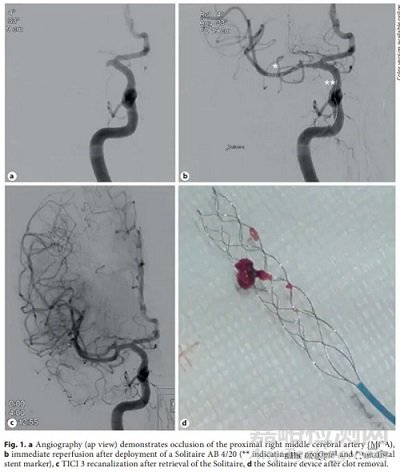

Solitaire:Solitaire FR(血流恢復)支架取栓器(Covidien/Medtronic,Dublin, Ireland)是第一個專用的血栓切除支架。之前有一種Solitaire AB(動脈瘤輔助)器械,用于建立臨時通路和取栓。

當前器械是第四代Solitaire X。它是一種鎳鈦合金支架,由鎳鈦合金片激光切割并成型為重疊的參數(shù)設計。幾何配置為閉合單元設計,具有頂點-頂點連接(如下圖)。支架有3、4和6 mm直徑可用,3 mm直徑的支架長度為20 mm,4 mm直徑的支架長度為20和40 mm,6 mm支架的長度為20、24和40 mm。支架在近端和遠端以及支架長度上均勻間隔5-10 mm處均有鉑金標記,用于可視化支架的打開和血栓整合。

參數(shù)設計導致支架覆蓋重疊,增加了血栓接觸。支架施加的徑向力也取決于血管直徑。

動物研究顯示Solitaire FR器械在移除血栓方面取得了高度成功。在100%的病例中觀察到TICI 3血流恢復,并且在大多數(shù)病例中實現(xiàn)了立即血流恢復。

單中心經(jīng)驗顯示,該器械在79%的前循環(huán)病例中實現(xiàn)了首次通過再通(TICI 2b/3),整體成功再通率為72.8%。另一項研究顯示,使用Solitaire器械的再通率為89%。初步研究中的并發(fā)癥率較低,腦內(nèi)出血率為2%,蛛網(wǎng)膜下腔出血率為4-6%。